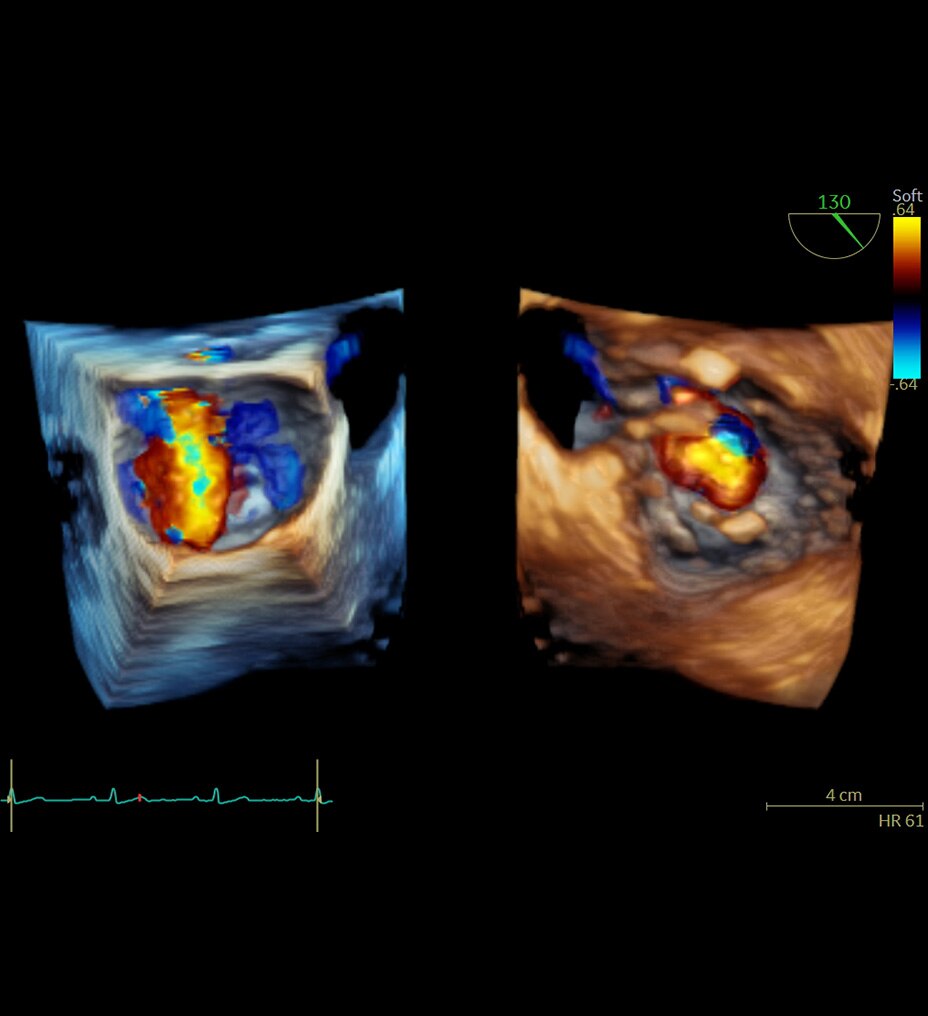

Un contraste d’image équivalent à l’imagerie CT sans rayonnement ionisant

L’IRM osseuse fournit un contraste d’image équivalent à l’imagerie CT sans rayonnement ionisant, ce qui en fait une alternative intéressante pour les patients pédiatriques et les patientes enceintes pour qui le rayonnement ionisant est déconseillé. En outre, elle offre une solution de repli lorsque des images CT longitudinales sont nécessaires, notamment en l’absence de systèmes CT à faible dose.